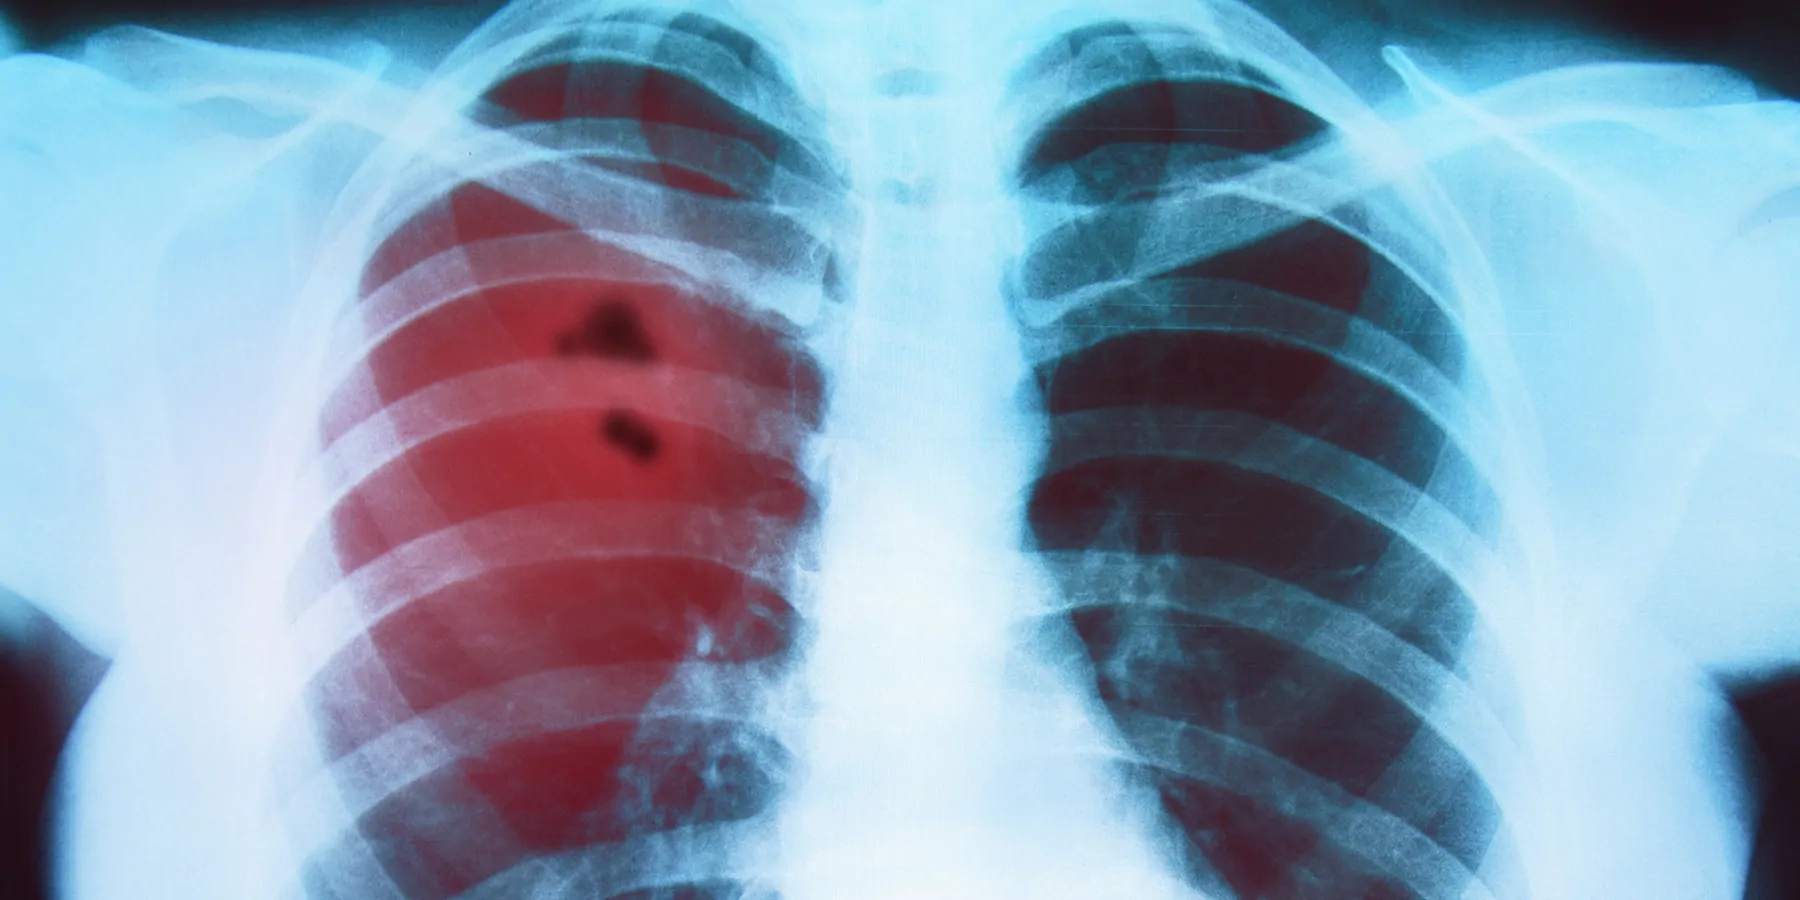

Perioperative Immunotherapy Significantly Improves NSCLC Outcomes

HOUSTON ? A regimen of presurgical immunotherapy and chemotherapy followed by postsurgical immunotherapy significantly improved event-free survival (EFS) and pathological complete response (pCR) rates compared to chemotherapy alone for patients with operable non-small cell lung cancer (NSCLC), according to results of a Phase 3 trial reported by researchers at The University of Texas MD Anderson Cancer Center.